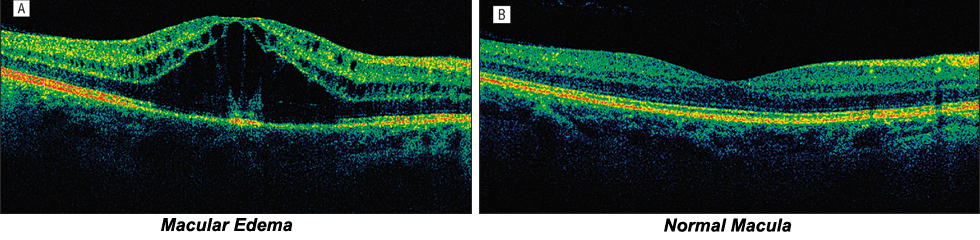

Macula OCT : A retinal scan test which allows detection of swelling in the center of retina (macula).

Focal laser treatment is used to treat macular edema (swelling) whereby small laser burns are placed in the area of leakages. These burns slow the leakage & reduce the amount of fluid in centre of retina. Laser treatment can reduce the risk of blindness by 90%. However laser treatment cannot restore vision that has been already lost. It mainly helps to stabilise the exiting vision.